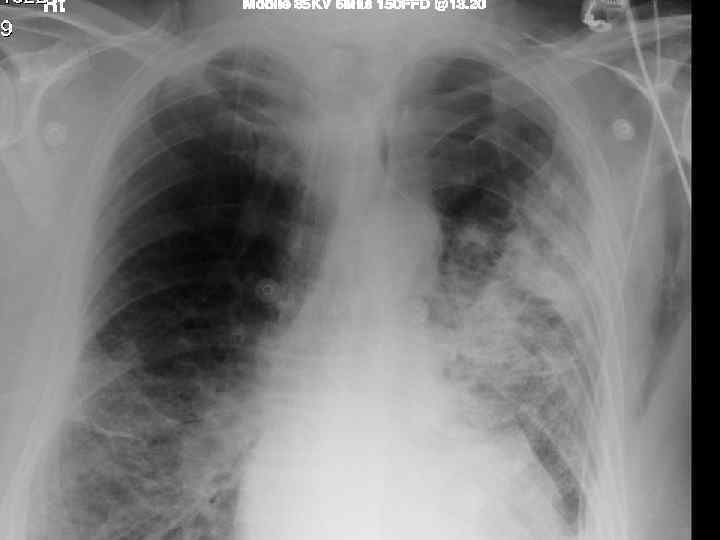

History n Mr X is a 74 year old Caucasian male n PC: Acute SOB n HPC: SOB episode began at 10 -11 am this morning gradually worsening, but suddenly became acutely worse. Noticed by neighbour. Ambulance blue lighted to AE resus

Examination n n n Anxious, gasping for breath, holding arms on trolley, Abdominal muscles used for breathing Central cyanosis Pulse 106 bmp regular HS I + II + 0 Apex beat laterally displaced Pitting right ankle oedema No sacral oedema

Respiratory R n n n L Resp rate 22 pm Trachea central Uneven lung expansion Hyperinflated upper chest Hyperresonant percussion Exp wheezing Insp crackles

Impressions n Pneumothorax n COPD/Fibrosing alveolitis n AHA n Congestive heart failure n Newly diagnosed Diabetes mellitus

Investigations. n CXR n CT n Arterial blood gases

Follow up n Unsuccessful referral to resp. physician n Successful discharge with: Chest clinic appointment (after 7 -10 days) n No air travel for 3 mths n Back to hospital if symptoms worsen n

Clinical features n Progressive breathlessness n Cyanosis n Pulmonary hypertension/cor pulmonale n Clubbing n Bilateral fine end insp. Crackles n X-ray shows ground glass appearance

Investigations n Chest X-ray n High res. CT scan n Respiratory function tests n Blood gasses n ANF, RF, ESR n Bronchoalveolar lavage n Biopsy